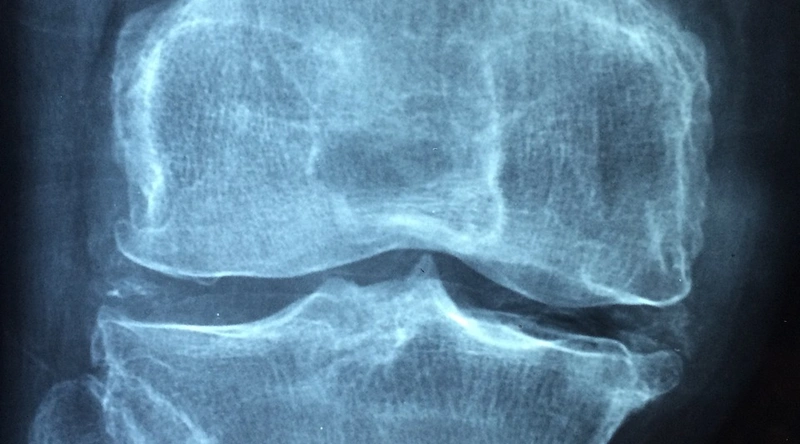

회전근개는 어깨 관절을 지지하는 여러 근육과 힘줄로 구성되어 있습니다. 이 부위에 염증이나 손상이 발생할 경우, 어깨와 견갑골 부위에 통증이 방사될 수 있습니다. 특히 팔을 들어 올릴 때 통증이 심해지는 경우가 많으며, 어깨를 움직일 때 불편함을 느낄 수 있습니다.

회전근개 손상의 경우, 초기에는 보존 치료가 우선시됩니다. 소염진통제나 물리치료를 통해 통증을 완화하고 근육의 회복을 도울 수 있습니다. 필요에 따라 전문가의 진단을 통해 수술적 치료를 고려할 수도 있습니다. 따라서 증상이 심해지기 전에 조기에 치료를 받는 것이 중요합니다.